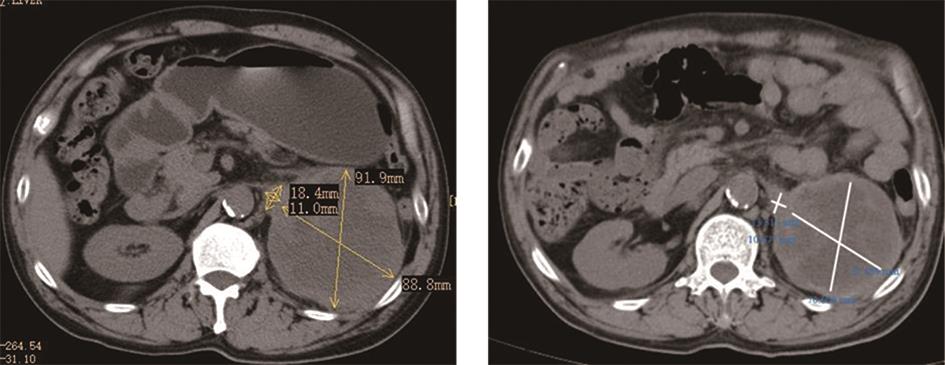

• 转移性上尿路上皮癌在维迪西妥单抗联合替雷利珠单抗新辅助治疗后行根治性肾盂癌切除术1例报道

2023, 48(8):1005-1008. DOI: 10.13406/j.cnki.cyxb.003299

摘要 (52) HTML (36) PDF 2.16 M (1929) 评论 (0) 收藏